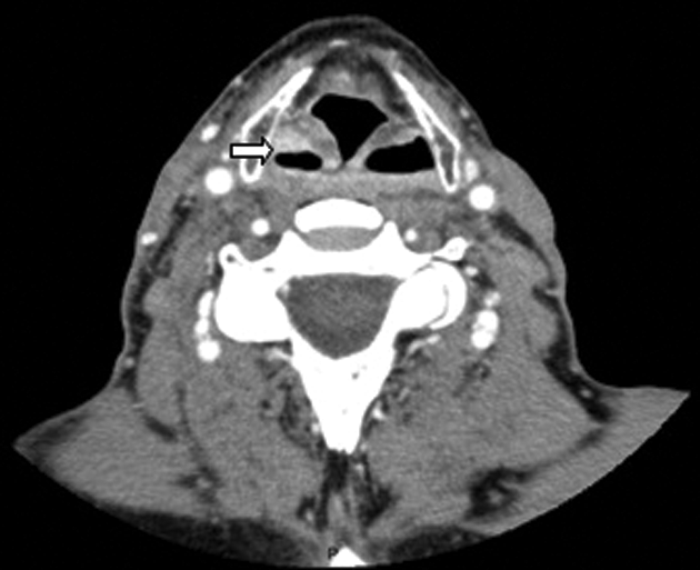

Figure 3: Contrast enhanced soft tissue axial CT demonstrating a buccal space abscess (white arrow).

A 17-year-old male presented with a one week history of left otalgia and general malaise. Otoscopy was normal, but there was asymmetric left tonsillar enlargement. His inflammatory markers were raised suggesting sepsis.

CT (Figure 8) demonstrated a left peritonsillar abscess. In addition Figure 9 shows the patient to have bilateral calcified stylohyoid ligaments. Pharyngitis / tonsillitis are common causes of referred otalgia. Additionally calcification of the stylohyoid ligament greater than 28mm can compress the glossopharyngeal nerve causing dysphagia, tinnitus and otalgia, a collection of symptoms termed as Eagle’s Syndrome.

Figure 8: Contrast enhanced CT demonstrating a left peritonsillar abscess (white arrow).